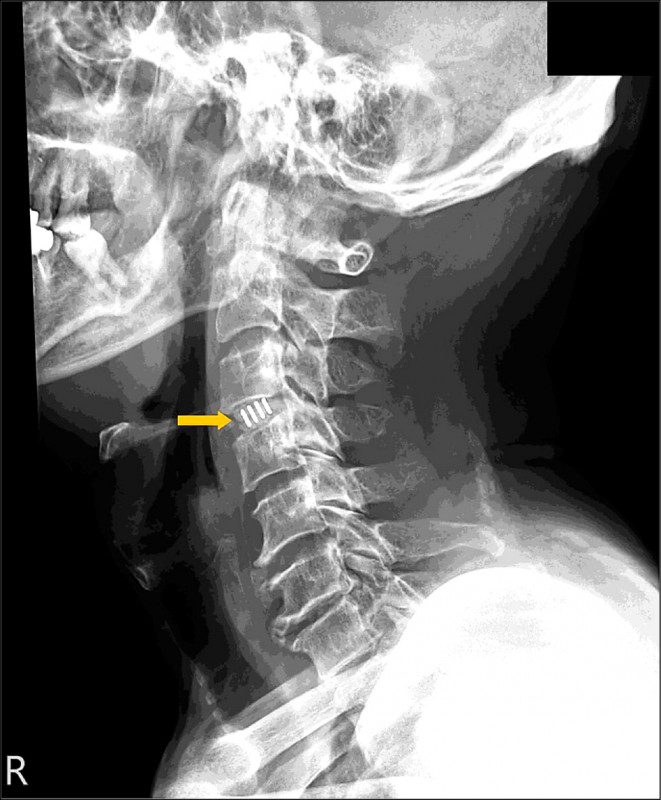

Jul 25, · 颈椎压迫了神经,要看它压迫的部位以及压迫的程度。通过核磁检查,就能发现,再看椎间孔位。 如果它的突出非常大,把椎间孔的神经压的非常死的话,而且经过保守治疗没有效的话,建议手术治疗,因为它突出的太多,已经把神经根已经压的丧失功能了。Jun 07, 17 · 颈椎病压迫脑神经的症状有哪些 1 症状一:主要有颈背疼痛、上肢无力、下肢乏力、手指发麻、行走困难、头晕、恶心、呕吐,甚至视物模糊、心动过速及吞咽困难等。 颈椎病的临床症状与病变部位、组织受累程度与个体差异有一定关系。 2 症状二:交感Sep 10, 19 · 颈椎压迫神经首先要解决症状,可以使用消除水肿、营养神经、改善循环等药物,改善神经压迫症状。对于有合适适应症的患者,可以进行颈部牵引。对于合并有疼痛、手麻的患者,进行针灸、推拿、拔罐、理疗的治疗。对于情况严重患者且符合手术指征,可行手术治疗。

May 30, 19 · 先到医院做颈椎磁共振检查,了解神经受压的程度、神经受压的范围和神经受压的部位。如果神经受压不严重,一般先进行保守治疗,包括牵引、按摩、理疗、针灸、拔罐、止痛活血药物治疗等。90%的患者通过保守治疗可明显缓解手麻的症状。如果神经受压非常严重,在保守治疗效果不好的情况下,建议进行手术治疗。有些人担心颈椎病手麻及无力是不是要瘫痪了,颈椎病Feb 25, · 颈椎压迫神经要区分是压迫的外周神经还是中枢神经系统。治疗方法有保守治疗和手术治疗两种。1、如果是神经根导致的上肢麻木疼痛,放射性疼痛,首选保守治疗。经过正规的保守治疗,比如针灸、按摩、药物、休息、理疗等能取得很好的效果。Oct 29, 18 · 问:颈椎压迫神经引起手麻,我老婆吃了一个老中医开的6付中药,没什么好转,他建议去医院挂神经科检查一下,他认为可能是两路神经动脉相碰到一起,才出现手麻,他说神经动脉碰一起可做微创手术,是真的吗,那这样的微创手术大概需要多少钱呢(女,48岁) 答:您好请问检查过吗?